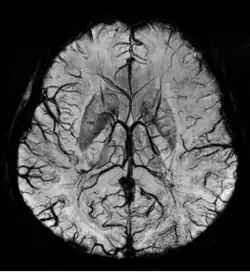

Im Gegensatz zur meist angestrebten signalreichen Darstellung der Gefäße gibt es auch die Möglichkeit, die Gefäße signalarm (dunkel) im umliegenden helleren Gewebe darzustellen. Dies wird beispielsweise für die Darstellung von Venen (MR-Phlebographie) mit T2*- und suszeptibilitätsgewichteten Pulssequenzen eingesetzt.